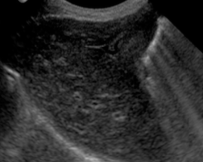

Écho de la vessie, vous avez cette image, qu'est-ce qui est recommandé de faire?

Soit il y a réellement un épaississement de la paroi ou pt que c'est juste pcq la vessie peu distendue => reprendre une écho après avoir donner à boire au patient (image de droite) => qd la vessie est bien distendue, sa paroi est normalement très fine